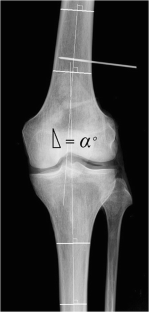

The aim of the present study was to describe the changes in the axis of the knee joint in both radiologically osteoarthritic and non-osteoarthritic knees, on the basis of angles measurable in standardized clinical short knee radiographs, in a cross sectional study of an epidemiological cohort.

From the third inclusion of the Copenhagen City Heart Study, 4,151 subjects were selected for standardized radiography of the knees. After censuring the inclusion, the resulting cohort was comprised of 3,488 individuals. Images were analyzed for radiological knee joint osteoarthritis (OA) and the anatomical femorotibial axis of the knee joint was measured.

The prevalence of knee joint OA in males was 27.9 % and 27.5 %, for the left and right knees respectively. In females this was 32.8 % and 36.4 %. The mean knee joint angles were 4.11° in males; and 5.45° in females. A difference of 1.3° was found between the genders. In non-osteoarthritic knees the increase in valgus orientation in relationship to increasing age was found to be 0.03° and 0.04° per year, respectively, for males and females. Likewise, Kellgren and Lawrence found that OA was seen to influence a shift towards varus of 0.55°–0.76° per level of OA.

Stratification in accordance with morphological severity of OA documented a clear tendency for the axis of the diseased knees to depart from the mean, primarily in the direction of varus. In knees exhibiting no signs of radiographic osteoarthritis we found a significant relationship between increasing age and a shift in the anatomical axis in the direction of valgus.